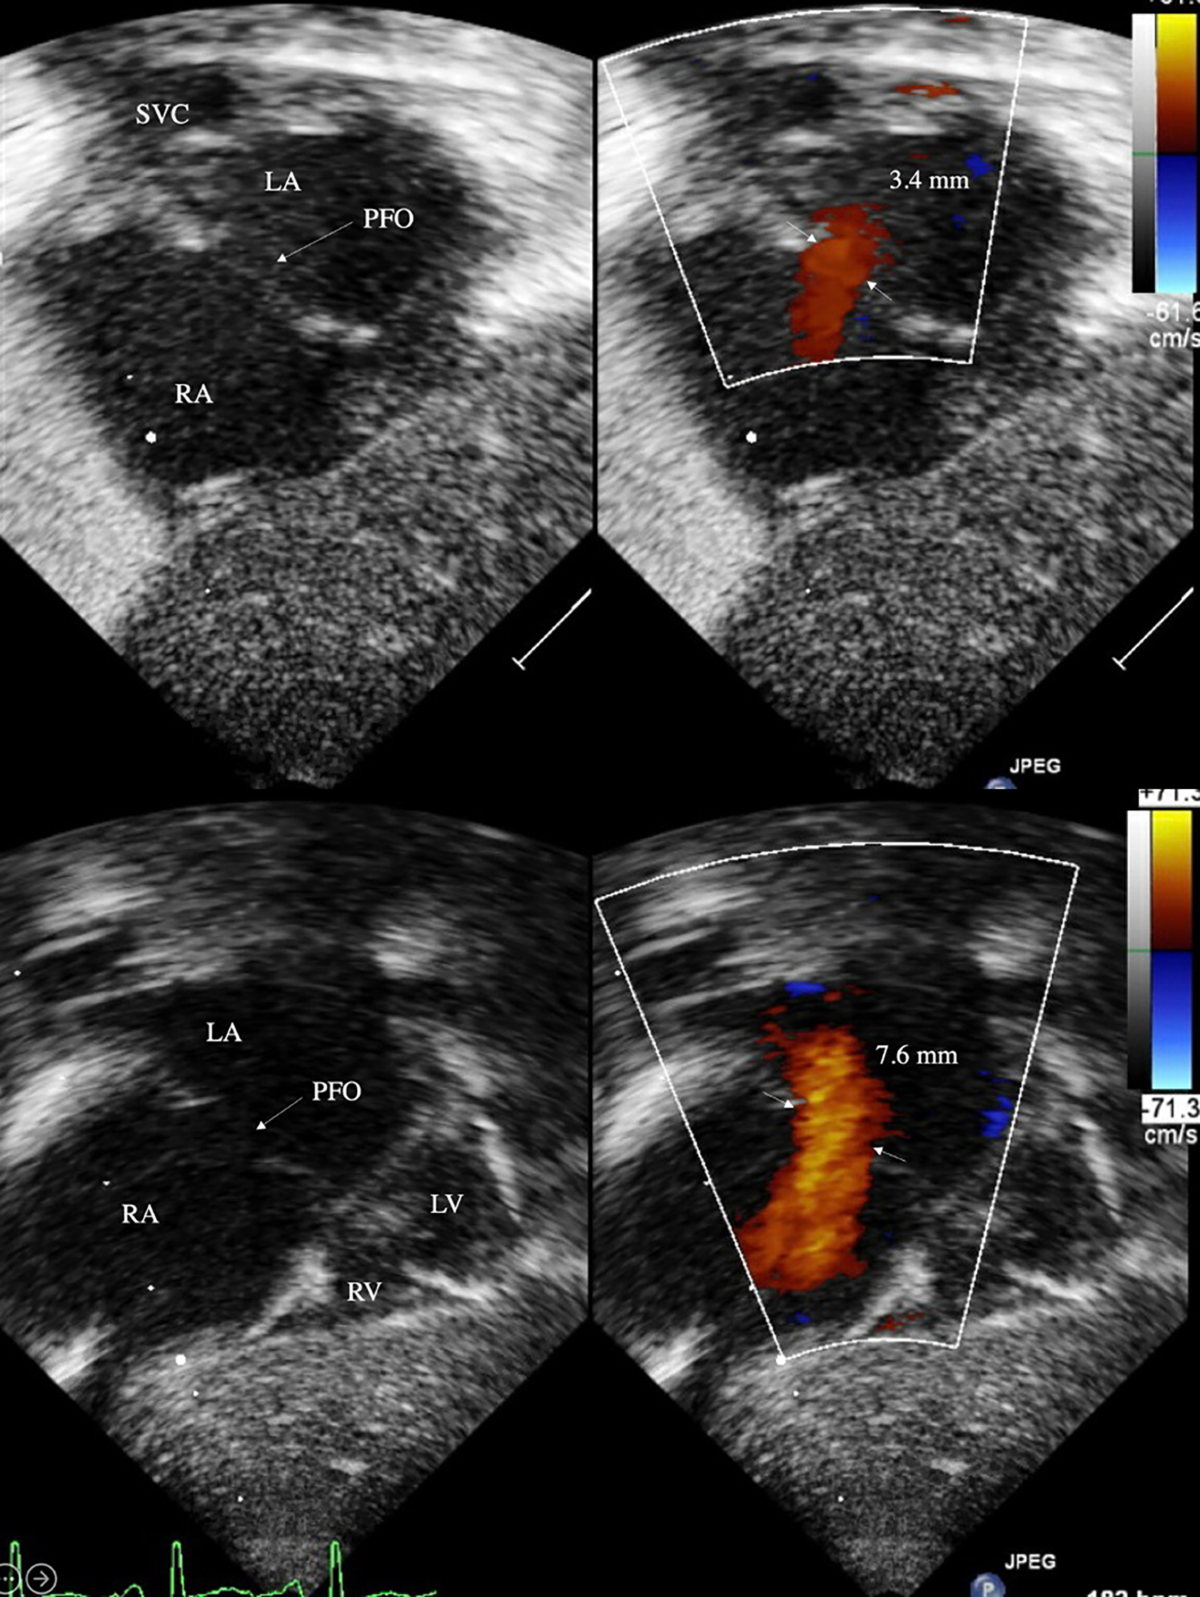

pfo in neonates sale